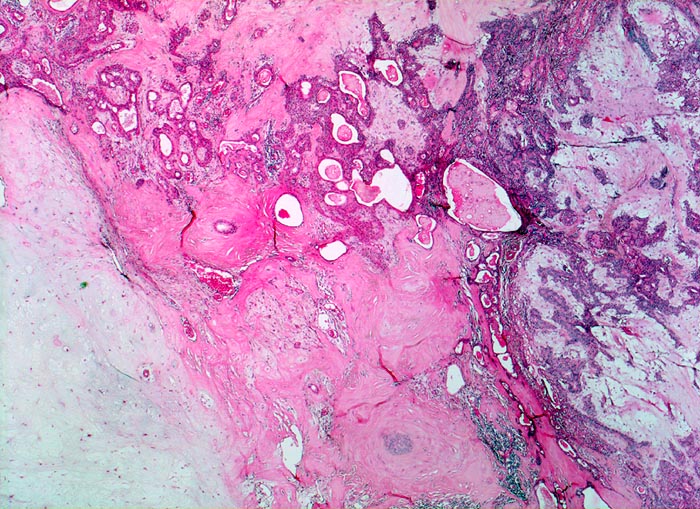

Mikroskopie und Histogenese:

Die architektonischen und zytologischen Befunde sind äusserst variabel. Pleomorphe Adenome bestehen aus einer duktalen epithelialen, einer myoepithelialen und einer mesenchymalen Komponente mit myxoider, hyaliner, chondroider oder ossärer Differenzierung. Der Prozentuale Anteil der verschiedenen Komponenten ist von Tumor zu Tumor sehr unterschiedlich. Gangstrukturen werden von einem einreihigen duktalen Epithel ausgekleidet. Das Gangepithel kann eine Plattenepithelmetaplasie mit Verhornung zeigen. Die Myoepithelzellen umgeben die epithelial ausgekleideten Gangstrukturen, bilden Nester, solide Zellplatten, Trabekel oder liegen einzeln im mesenchymalen Stroma. Die Morphologie der Myoepithelien ist sehr variabel (spindelig, plasmazytoid, epitheloid, sternförmig oder basaloid).

Histogenetisch handelt es sich wahrscheinlich um einen rein epithelialen Tumor, dessen mesenchymale Komponente von den neoplastischen Myoepithelzellen gebildet wird.

• Scharf begrenzter bekapselter Tumor bestehend aus epithelialen, myoepithelialen und mesenchymalen Anteilen.

• Das Epithel bildet duktale Strukturen, welche von reichlich Myoepithelien umgeben werden.

• Epitheiale Gänge werden ausgekleidet von kubischen luminalen Zellen und einer oder mehreren äusseren Schichten myoepithelialer Zellen.

• In den stromareichen Arealen rechts finden sich plasmazytoide Myoepithelzellen mit reichlich eosinophilem Zytoplasma und einem exzentrisch gelegenen runden Kern.

• Die stromale Komponente ist teils mukoid, teils hyalinknorplig, teils hyalinisiert bindegewebig.